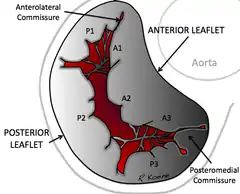

In Carpentier's classification of a mitral valve, both the posterior and anterior mitral valve leaflets are divided into eight segments: P3 (medial scallop), P2 (middle scallop), P1 (lateral scallop), A3 (anteromedial segment), A2 (anteromedial), A1 (anterolateral), PMC (posteromedial commissure), ALC (anterolateral commissure).[7] Mitral leaflet thickness is usually about 1 mm but sometimes can range from 3–5 mm.[7][8]